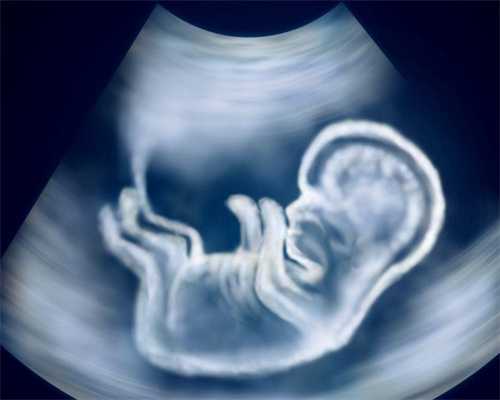

在湖南使用第三代试管婴儿辅助怀孕的费用大概在80000-100000元。第三代试管婴儿是通过单精子卵胞浆内注射受精的。另外需要冷冻胚胎和胚胎复苏,主要针对染色体异常或致病基因的遗传性患者。

第三代试管婴儿是在第一代和第二代试管婴儿的基础上发展起来的,所以要先促排卵。等卵泡成熟后,取卵,随后使用单精子显微注射到卵细胞浆内卵泡,形成胚胎,培养成囊胚,进行活检。选择染色体无异常或基因无异常的胚胎进行宫内移植,阻断遗传病传给后代。所以第三代试管婴儿的费用比第一代试管婴儿和第二代试管婴儿要高。